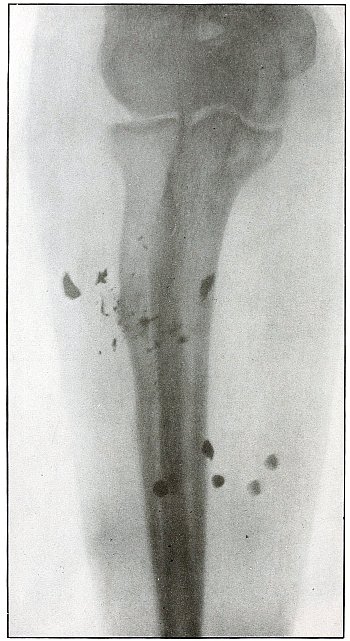

Plate 66.

_

[Pg 143]

Rifle—Plate 66.

LOWER EXTREMITY.